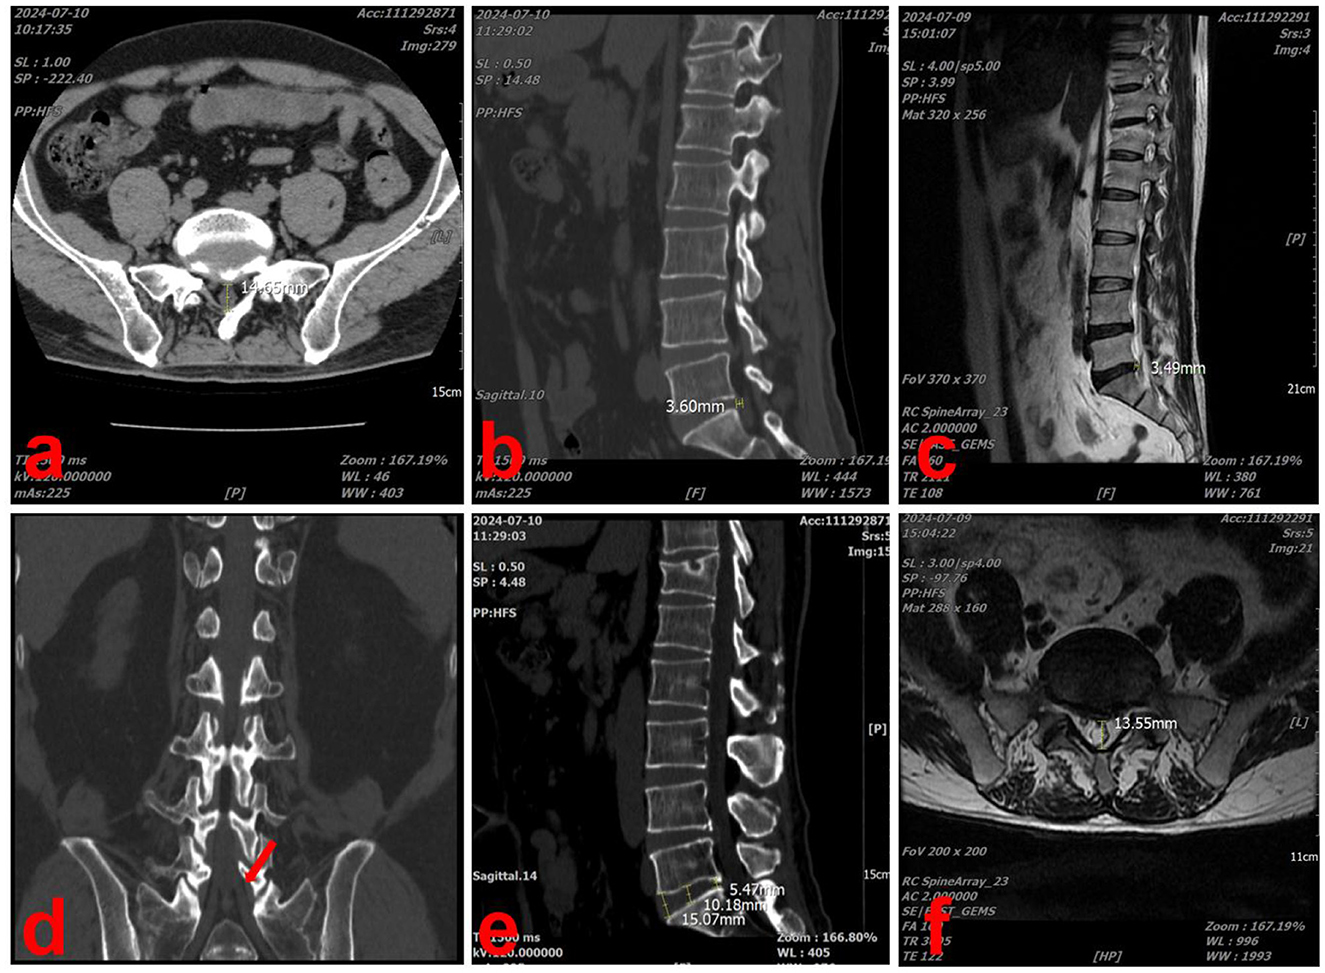

At the most recent follow-up, on July 9, 2024, the patient underwent CT and magnetic resonance imaging (MRI) of the lumbar spine, which revealed significant resorption of the herniated disc. In the sagittal section of the L5/S1 intervertebral space, the herniated disc measured 3.60 mm in length and the height of the lumbar intervertebral space was 10.27 mm (Figures 4b, e). In the cross-section, the diameter of the spinal canal at the L5/S1 level was 14.65 mm (Figure 4a). In the coronal section, there was no longer compression of the S1 nerve root by the herniated disc (Figure 4d). The results of MRI were similar to those of CT, though minor discrepancies may have arisen due to measurement and positional factors (Figures 4c, f). The patient's LDH classification was downgraded from MSU3-AB to MSU2-A and secondary lumbar spinal stenosis was alleviated.

Figure 4

Medical imaging collage showing six diagnostic images labeled a to f. Image a displays an axial CT scan of the abdomen. Image b is a sagittal CT scan of the spine with a highlighted measurement. Image c is an MRI of the lumbar spine showing vertebrae structure. Image d is a coronal CT scan of the pelvis with an arrow indicating a specific area. Image e is another sagittal CT of the spine with measurements. Image f is an axial MRI of the lumbar region with vertebral details.

Figure 4. Lumbar spine CT and MRI scans performed at the last visit (2024-07-09). (a) In the CT cross-section, the diameter of the spinal canal at the L5/S1 level was 14.65 mm. (b) In the CT sagittal-section, the herniated disc measured 3.60 mm in length. (c) In the MRI sagittal-section, the herniated disc measured 3.49 mm in length. (d) In the coronal section, there was no longer compression of the S1 nerve root by the herniated disc (red arrow). (e) In the CT sagittal-section, the height of the lumbar intervertebral space was 10.27 mm. (f) In the MRI cross-section, the diameter of the spinal canal at the L5/S1 level was 13.55 mm.

The patient received Chuzhen treatment for 1 month at the hospital and 3 years at home. The patient's symptoms were significantly relieved after 3 years of follow-up. His VAS pain score decreased from 8 to 0, ODI decreased from 45 to 5, and the JOA score increased from 7 to 24. Moreover, imaging findings also demonstrated notable improvements, including a 64.8% shortening of the sagittal herniated length, 19.2% enlargement of the spinal canal diameter, and no significant changes in intervertebral height. This case highlights the long-term efficacy of Chuzhen therapy for LDH and suggests that its therapeutic mechanism may be related to the spontaneous resorption of disc herniation observed during the three-year follow-up. The 3-year regression timeline aligns with faster-resorbing cohorts, possibly enhanced by Chuzhen therapy's proposed neovascularization effects. However, without controls, we cannot exclude natural history.